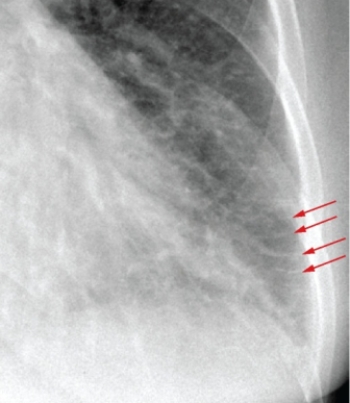

The red arrows in this image highlight a finding that is associated with: